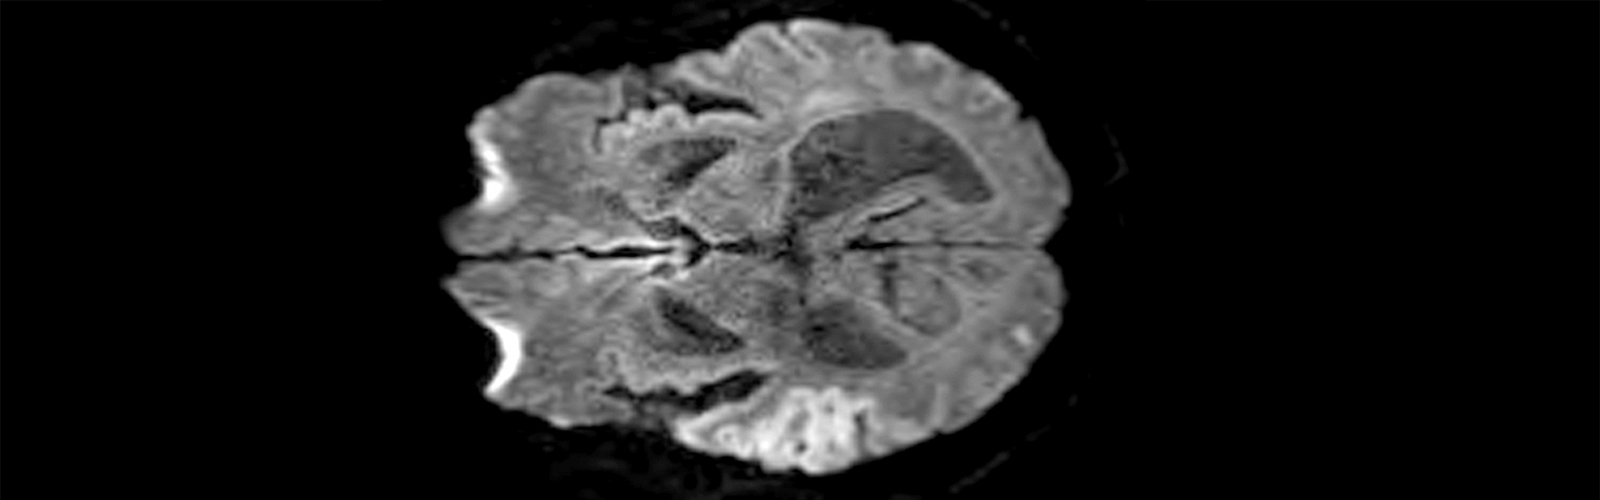

Later on, a doctor looked at the computed tomography angiography scan of my brain and said to me, “You should not be able to do anything with your left arm,” pointing to the scan showing a dark area without signs of blood flow on the right side of the brain, which controls movement on the left side.